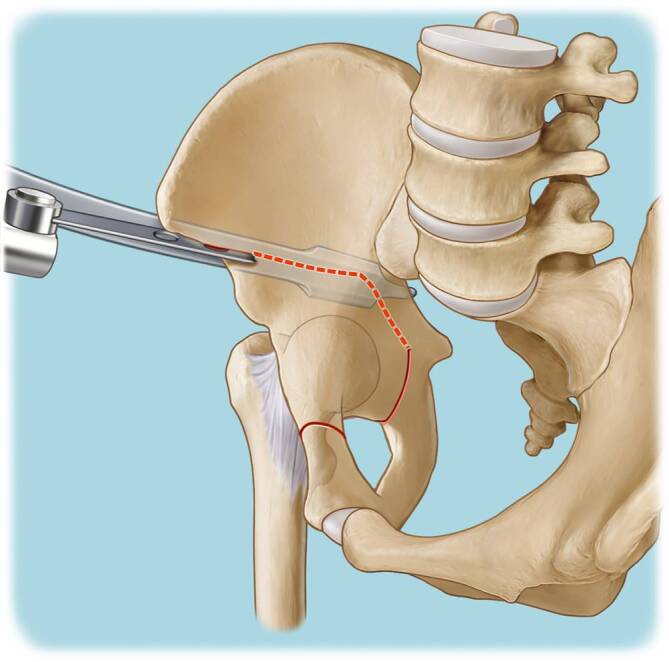

Vor der Operation ist die digitale Planung obligat, um das optimale Ausmaß der Korrektur zu bestimmen und eine postoperative Über- oder Unterkorrektur zu vermeiden. In der a.-p.-Beckenübersicht sind ein postoperativer LCE-Winkel von 30°, ein positiver Tragflächenwinkel (Norm zwischen 3 und 13°), ein Femurkopfextrusionsindex ≤ 27 % (Norm von 17° und 27°) und ein antevertiertes Azetabulum die Zielwerte für die Korrektur (Abb. 1). Die azetabuläre Version kann aktuell jedoch nicht mittels der Planungssoftware geplant werden. Diese sollte jedoch präoperativ evaluiert werden, und in diesem Zusammenhang sollten präoperativ der „acetabular wall index“ und Retroversionszeichen wie „cross-over sign“, „posterior wall sign“ und der „acetabular wall index“ erhoben werden.

Außerdem sollte, wenn möglich, eine mediale Dysplasie vermieden werden. Bei sehr kurzer azetabulärer Knorpeltragfläche muss individuell ein Kompromiss zwischen medialem und lateralem CE-Winkel sowie dem Tragflächenwinkel gefunden werden, um eine nahezu „normale“ Überdachung zu erreichen.

Die Schambeinosteotomie sollte mit einer kleinen oszillierenden Säge begonnen und mit einem geraden Osteotom abgeschlossen werden, um eine unkontrollierte Spaltung des Schambeins zu vermeiden. Die Schambeinosteotomie sollte ebenfalls nach kaudal und medial gerichtet sein. Eine zu vertikale Ausrichtung der Schambeinosteotomie kann zu einer Lateralisierung des Pfannenfragments führen, wodurch evtl. eine Medialisierung des Schambeins eingeschränkt sein kann.

Die supraazetabuläre Osteotomie sollte mindestens 3 cm kranial der Hüftgelenkpfanne durchgeführt werden, um genügend Raum für die Insertion der 2 Schanz-Schauben zu schaffen und eine stabile Schraubenfixation zu ermöglichen.

Die retroazetabuläre Osteotomie sollte in der Mitte der hinteren Pfannensäule liegen und nicht zu nahe an der Hüftpfanne durchgeführt werden. Der Knochen direkt hinter der Hüftpfanne ist sehr dick und schwierig komplett zu osteotomieren. Wenn die retroazetabuläre Osteotomie nicht vollständig durchgeführt wird und bei der Reorientierung des Azetabulumfragments zu viel Kraft über den Laminaspreizer aufgebracht wird, besteht die Gefahr, eine intraazetabuläre Fraktur durch die Fossa acetabuli zu induzieren.